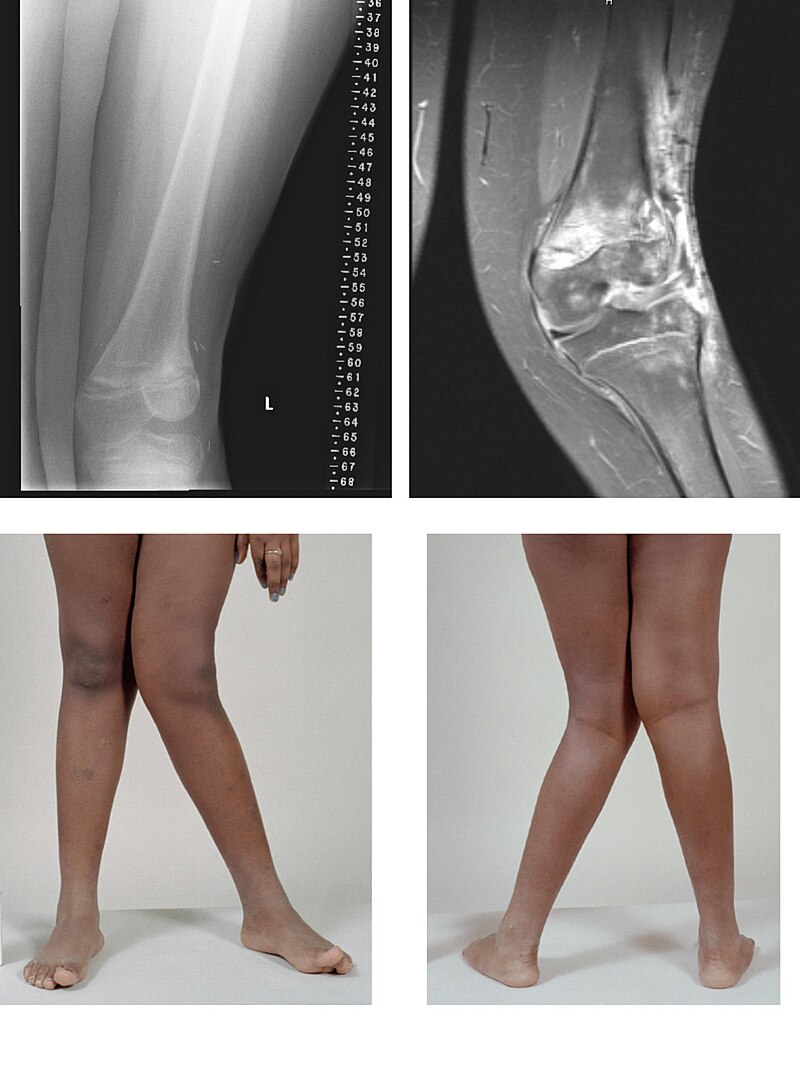

File: Valgus.jpg (114 KB, 800x1067)

114 KB

114 KB JPG

>>76773006

>how insecure

flat footed hands have written this post (it's the same bot but u get the joke right?)

https://en.wikipedia.org/wiki/Tibialis_anterior_muscle

>The muscle helps maintain the medial longitudinal arch of the foot.

>The movements of tibialis anterior are dorsiflexion and inversion of the ankle

https://en.wikipedia.org/wiki/Tibialis_posterior_muscle

>The tibialis posterior muscle is a key muscle for stabilization of the lower leg. It also contracts to produce inversion of the foot, and assists in the plantarflexion of the foot at the ankle.[3] The tibialis posterior has a major role in supporting the medial arch of the foot. Dysfunction of the tibialis posterior, including rupture of the tibialis posterior tendon, can lead to flat feet in adults, as well as a valgus deformity due to unopposed eversion when inversion is lost.[4][5]

not only flat footed but also valgus knee-d :D